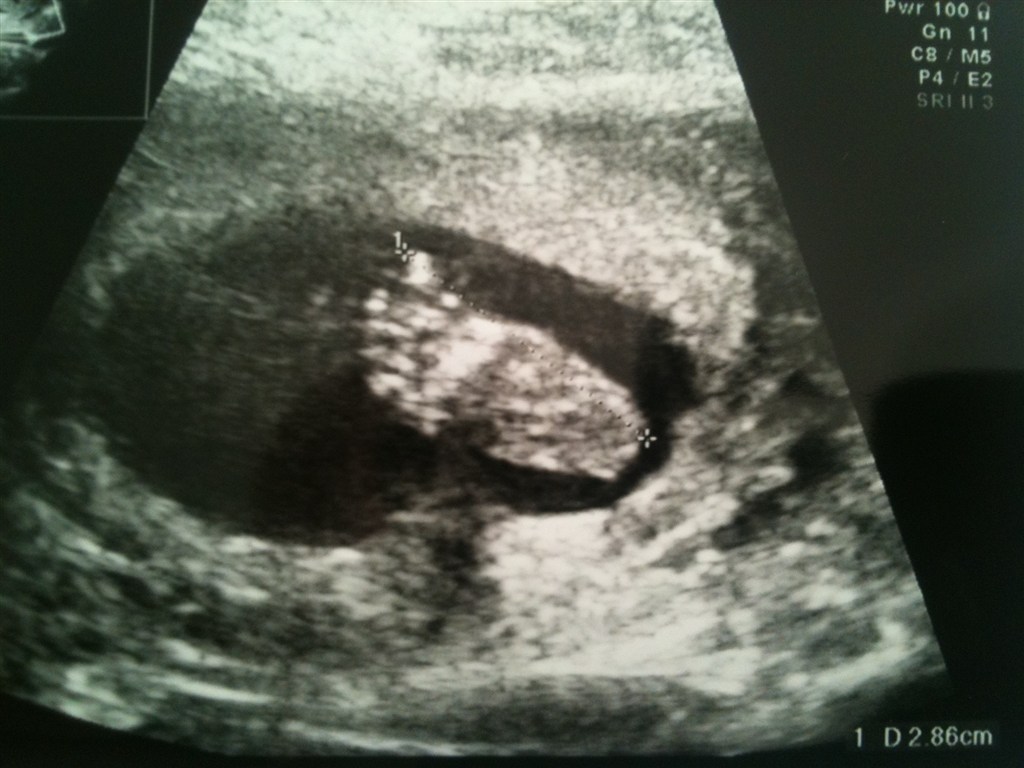

det grinet hun lidt af, hehe.. Hun tilbydte mig en ekstra tid.. nu er der jo læge tid i uge 25 og jordemoder igen i 28.. så det var ok.. ligger lige nogle billeder op af den lille..